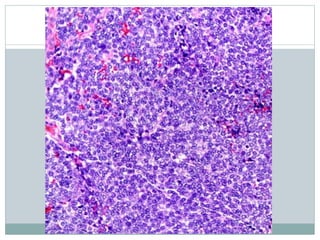

• #11 Ewing sarcoma (ES) is a highly cellular, high-grade sarcoma with a dense, solid to sheet-like distribution of cells, as depicted. Most tumors are diagnosed on small biopsy prior to treatment with chemotherapy, and large, preserved sections, as shown, are uncommon.

• #12 The tumor is classically very cellular cells arranged in diffuse sheets or lobules. Tumor cells and nuclei are generally uniform. Stromal vessels are commonly found.